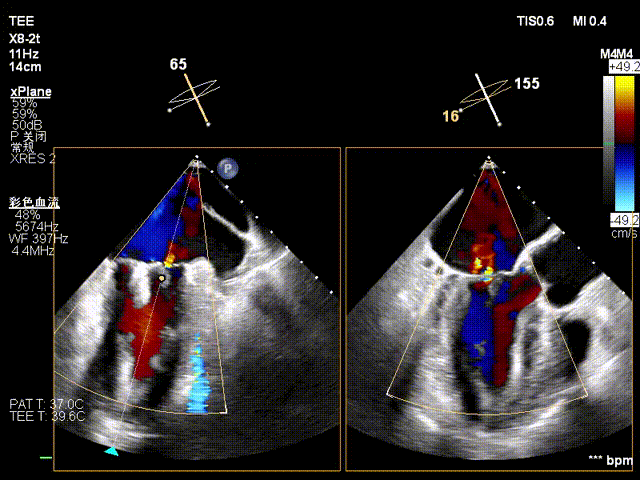

术中操作(关键步骤超声)

在全麻下,于心尖入路完成ValveClamp®装置植入。术中多学科团队密切配合,超声全程实时指导操作。最终,于2偏3区成功植入一枚Ⅲf夹子,一次夹合完成。前叶夹合量12mm,后叶夹合量10mm,反流降至1+,导管操作时间30分钟。术后平均跨瓣压差3mmHg。

术前反流 术后反流

术中剪影